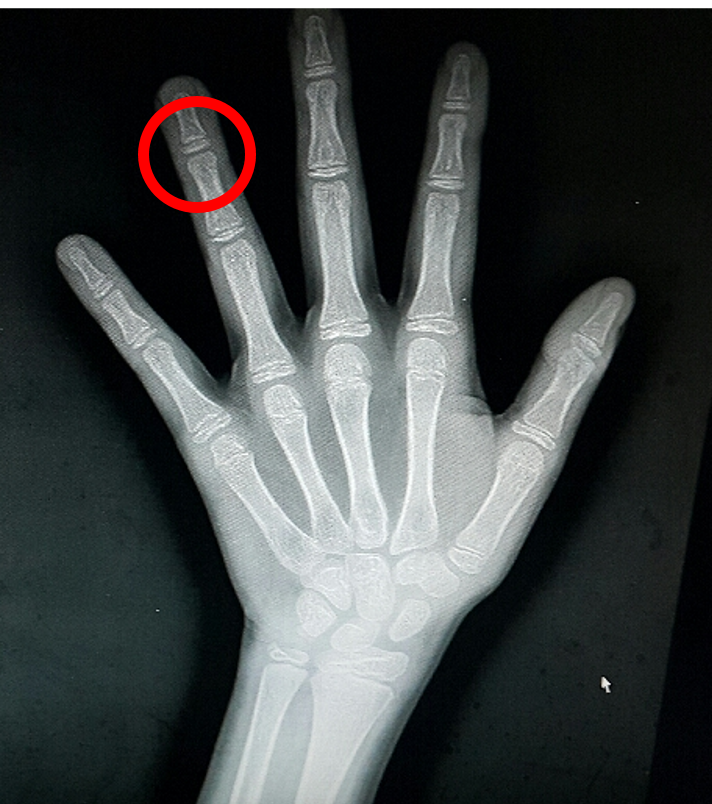

근데 아무리 봐도 왼손 네번째 손가락 끝마디가 구부러져서 펴지질 않음

이 저런것 엑스레이 다시 봐보자함 (그동안 드레싱 할떈 실물로 못보고??)

엑스레이 주섬주섬 찾아서 보더니 한마디 함

"아 맞다"

미친 추가수술(핀박음)